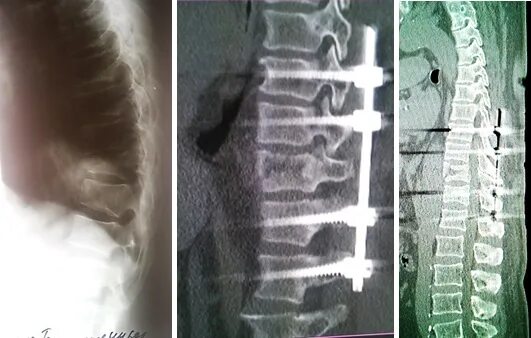

Перелом позвонка инвалидность